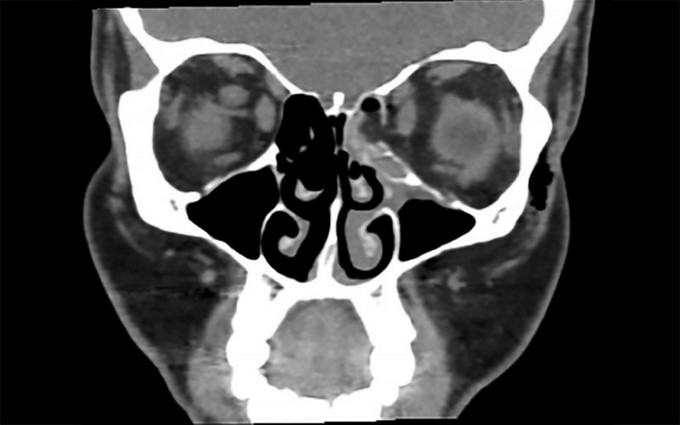

En el hospital por medio de una tomografía, los especialistas descubrieron una fractura en el ojo izquierdo y se pudo ver que el hueso que rodea el ojo izquierdo se había roto.

Los médicos destacaron que la fractura fue limpia y relativamente fácil de tratar. Le recetaron analgésicos y no necesitó cirugía.

Image: Fractura después de sonarse (BMJ Case Reports 2018)